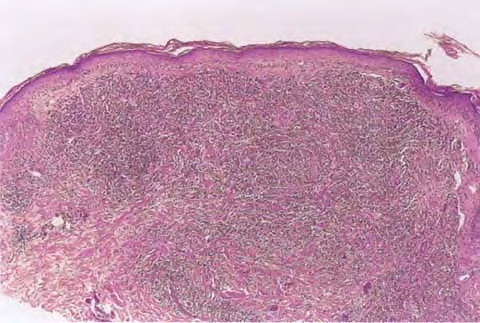

Mycosis Fongoïde =التفطر الكمئي